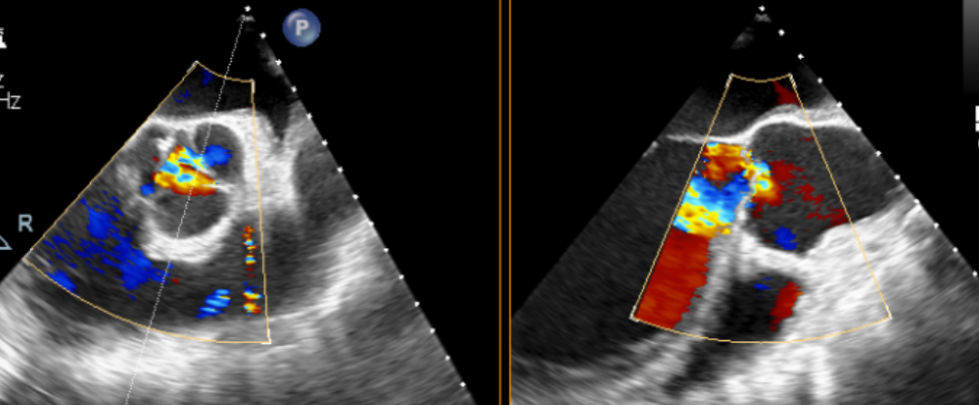

术前超声

术后超声

手术过程顺利,器械操作用时仅10分钟。术中通过造影确认右冠窦居中,定位件准确入窦,瓣膜释放顺利。经超声评估,无瓣周漏,手术过程衔接流畅,未出现其他特殊情况。

术后患者恢复良好,心功能显著改善。影像复查显示瓣膜功能正常,无反流及瓣周漏,未见心律失常、出血等并发症。平均主动脉跨瓣压差5mmHg,整体状态稳定,心功能与生活质量均有明显提升。